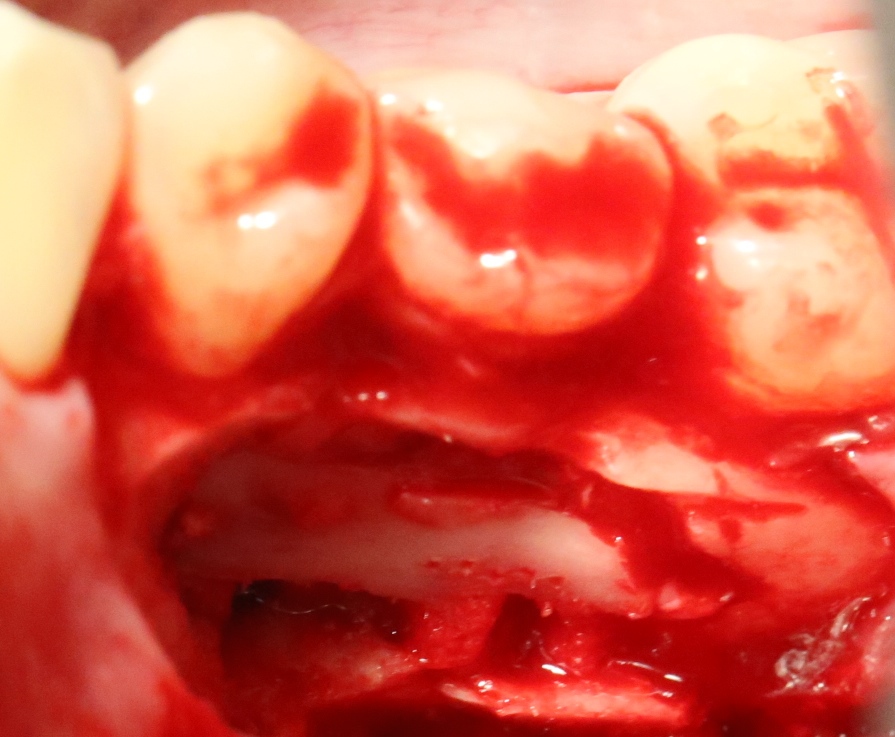

Костная «дверца» на время отделяется и убирается в физраствор, а мы видим следующее:

Это фолликулы и, частично, коронковые части сверхкомплектных зубов.

Теперь аккуратно нам нужно выделить сами зубы:

А вот они! Далее мы руководствуемся главным правилом хирурга-стоматолога: